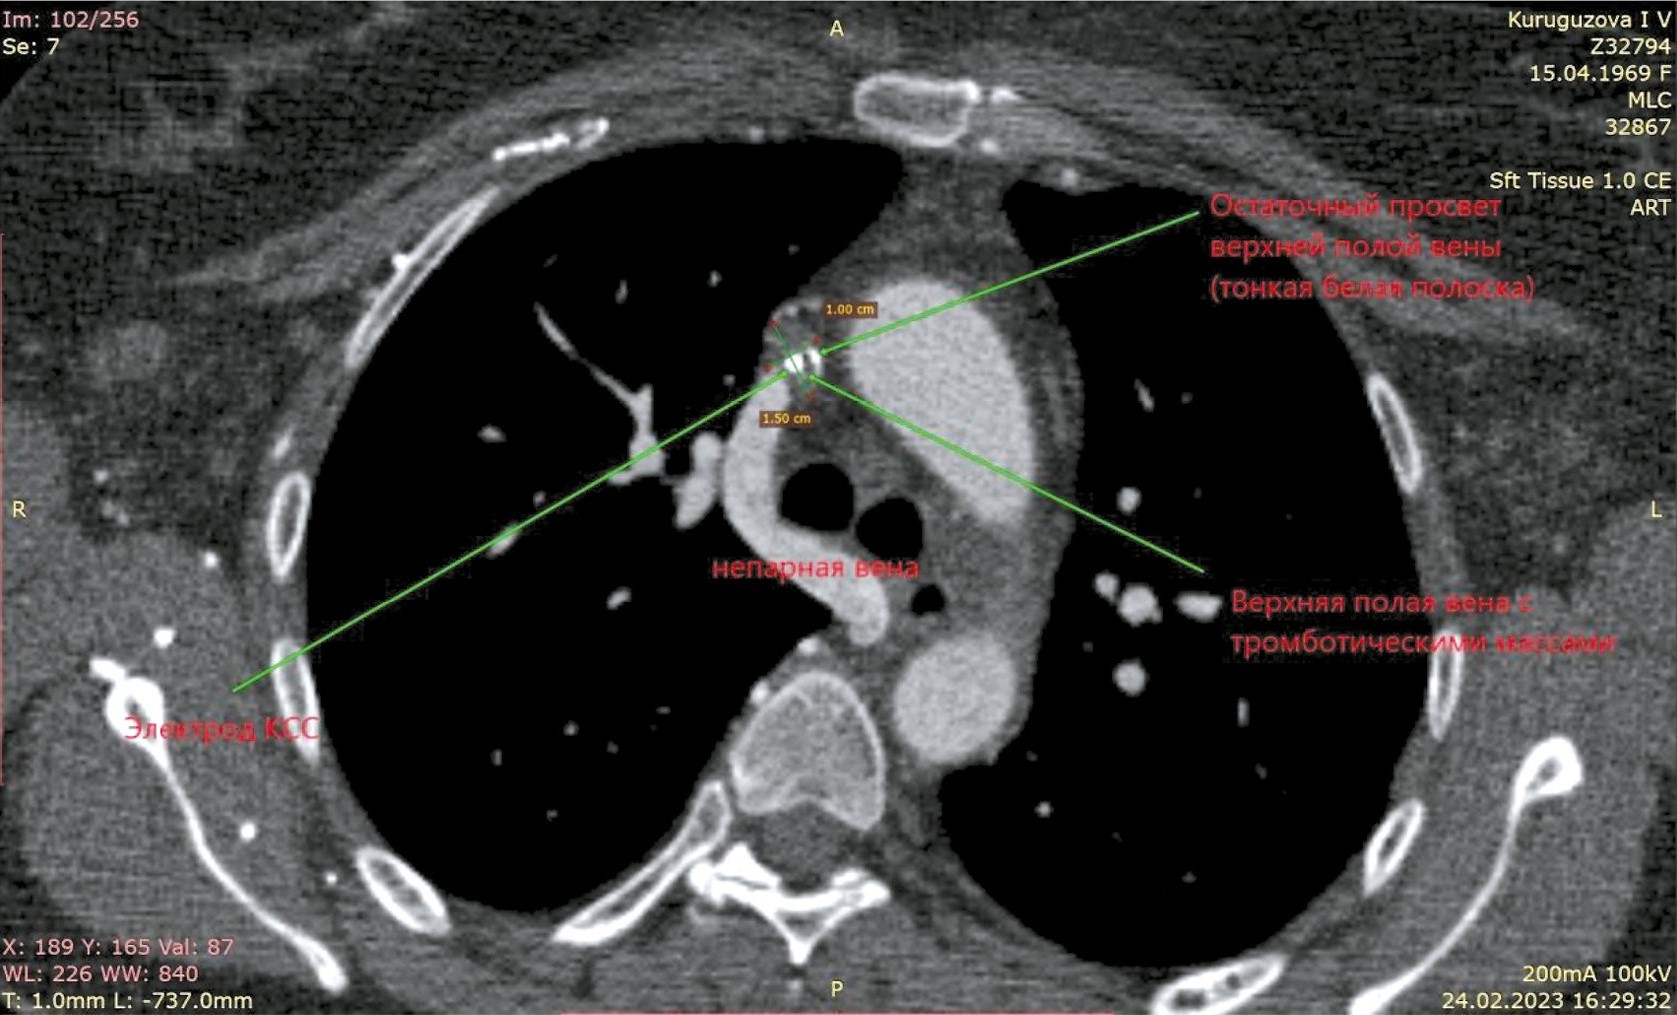

Рис. 2. Компьютерная томограмма пациентки К. Верхняя полая вена с тромботическими массами, остаточный просвет. Непарная вена расширена.

Fig. 2. Computed tomography of patient K. Upper vena cava with thrombotic masses, residual lumen. The neparietal vein is dilated.

Обращает на себя внимание выраженная задержка контраста в венах правой верхней конечности, куда вводилось контрастное вещество. Имеется богатая ветвь венозных анастомозов в мягких тканях грудной клетки, паравертебрально. ВПВ уменьшена в диаметре, её просвет практически полностью заполнен тромботическими массами от уровня впадения левой подключичной вены до места впадения непарной вены, сохранён просвет в виде узкой (1×4 мм) полулунной щели вдоль электрода. Непарная вена расширена, имеет диаметр до 10 мм и практически полностью обеспечивает верхний приток крови к правому предсердию. Основное возвращение крови к сердцу происходит через нижнюю полую вену, заполнение контрастом которой заметно отсрочено. Заключение: картина тромбоза/субтотальной облитерации ВПВ с организацией коллатерального венозного кровотока. Состояние после установки электрокардиостимулятора (ЭКС). Дилатация левых отделов сердца.